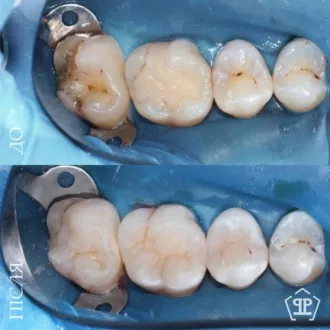

Пациент обратился с жалобами: чувство холодного воздуха и неприятные ощущения языком в области старых пломб. Было произведено полноценное удаление инфицированных тканей с последующим реставрированием зубов согласно анатомических особенностей.